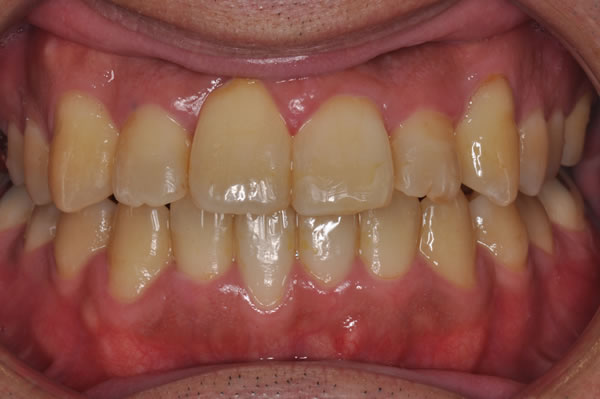

治療前(初診)

治療後